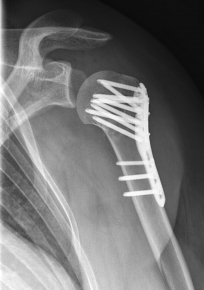

Picture: Here is a subcapital upper arm break in a young woman. An angle stable plate osteosynthesis was performed to stabilize the head in correct position to the humeral shaft and shoulder joint. Especially in young patients, We strive to treat non-invasively and as gently as possible. This possibility is often due to the bone quality in young as opposed to older people.